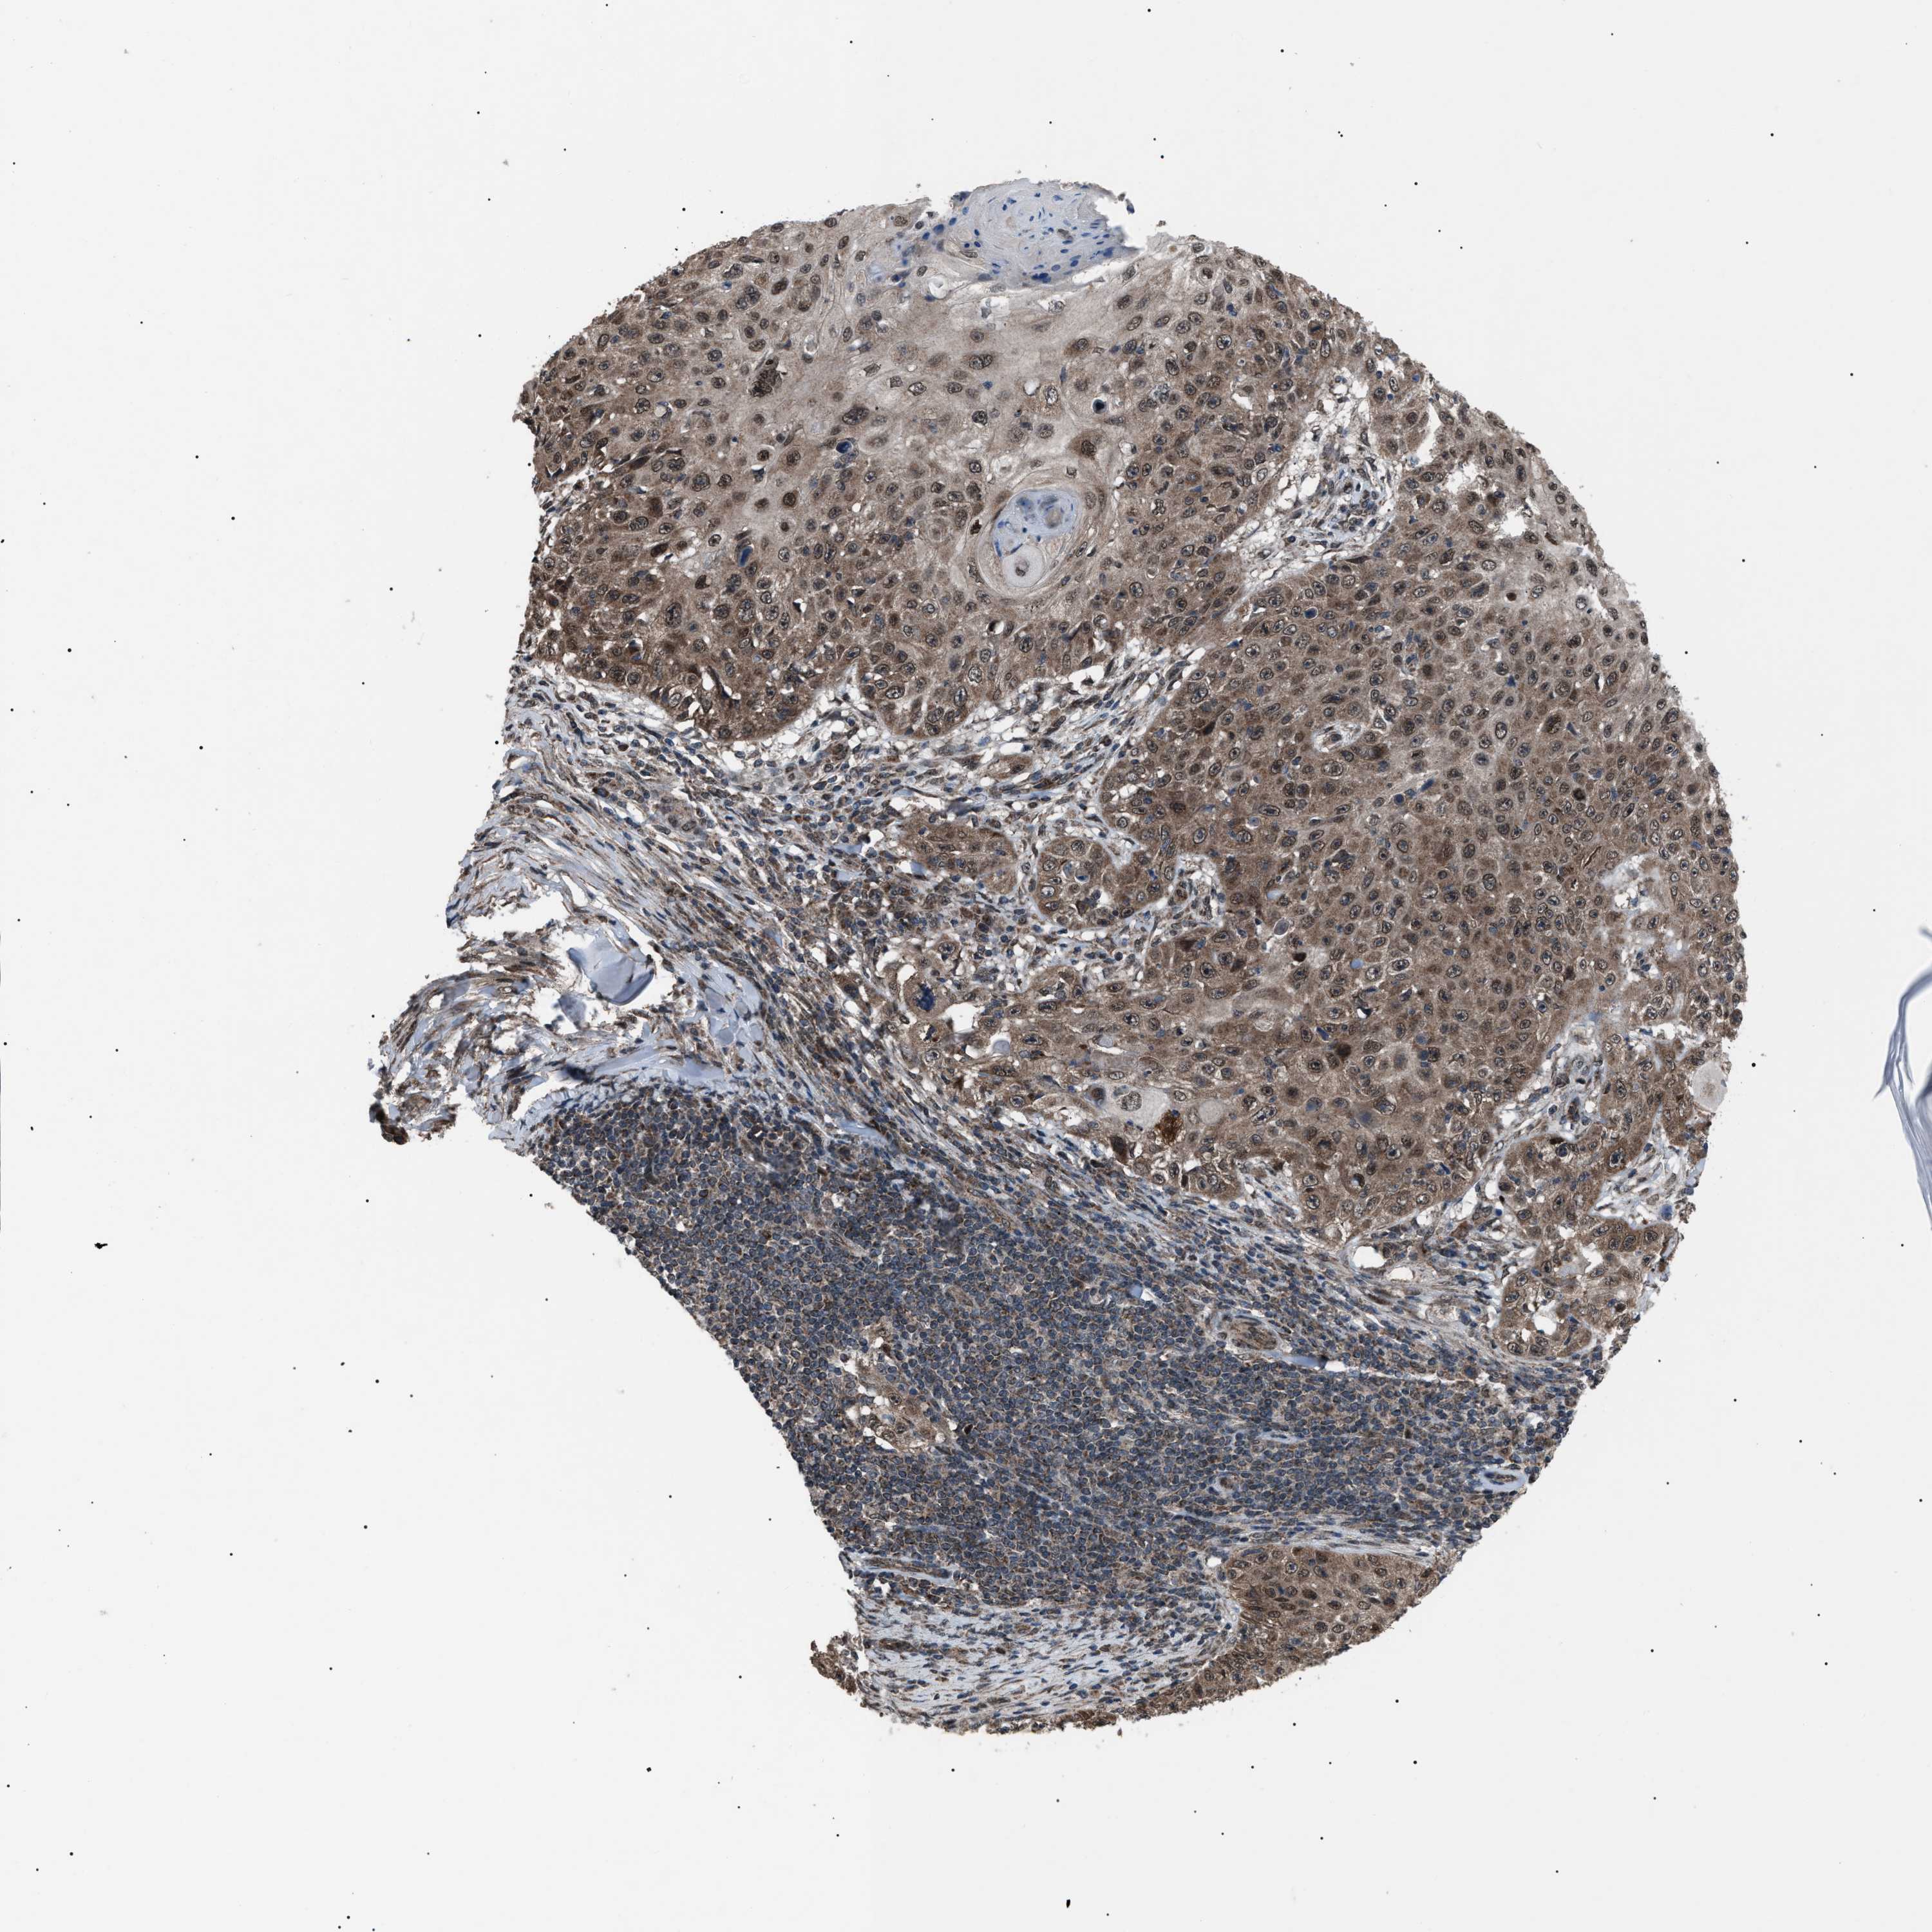

CANCER SKIN CANCER Show tissue menu

Basal cell and squamous cell cancer

SKIN CANCER - Protein expressioni

A mouse-over function shows sample information and annotation data. Click on an image to view it in a full screen mode. Samples can be filtered based on level of antibody staining by selecting one or several of the following categories: high, medium, low and not detected. The assay and annotation is described here.

Each image is clickable and will lead to virtual microscopy that enables deeper exploration of all samples and also displays staining intensity scores, fraction scores and subcellular localization as well as patient and tissue information for each sample.

Antibody HPA019469

Staining

High

Intensity

Strong

Quantity

>75%

Location

Nuclear

Basal cell carcinoma

Squamous cell carcinoma, NOS

Squamous cell carcinoma, metastatic, NOS